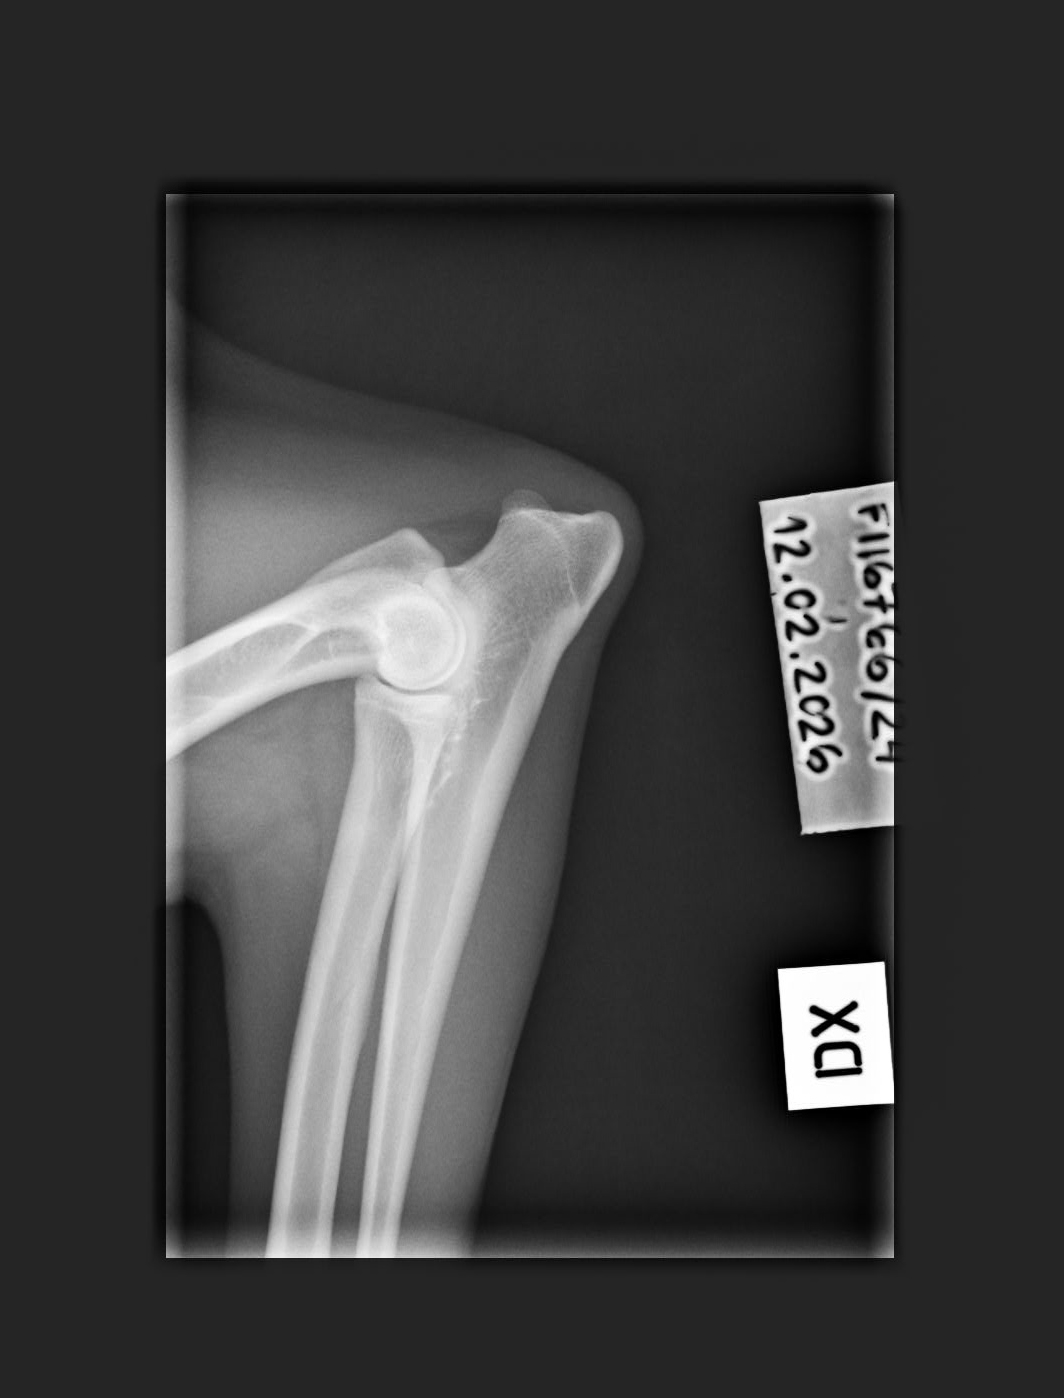

C/B |

1/0 (see Notes) |

- Finnish Kennel Club's elbow x-ray report Dec '25: Signs suggestive of medial coronoid disease; further information about the condition of the joints can be obtained, if necessary, by computed tomography (CT) examination

- Finnish Kennel Club's elbow CT report Feb '26: A small amount of new bone formation around the medial coronoid process of the left elbow